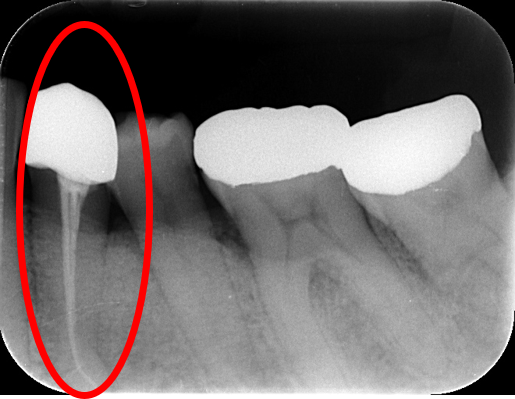

- レントゲン撮影で歯の神経に病気がみられる

- レントゲン写真で状態を確認する

クスリを詰める - レントゲン写真で状態を確認する